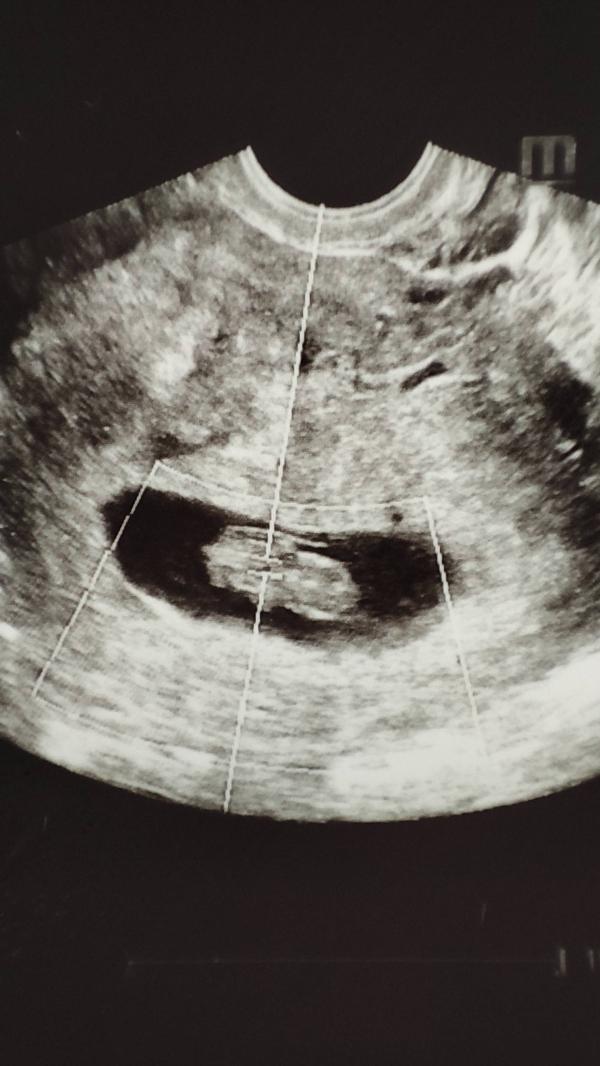

Первая фотография человечка

14.04.24

Услышала сердечко...